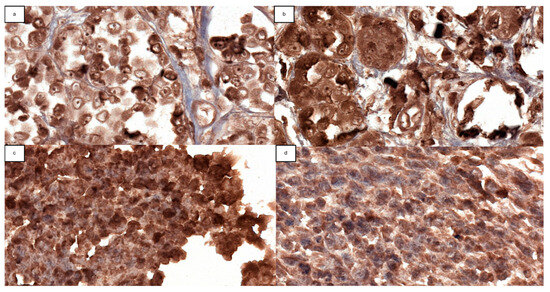

4.2. Immunohistochemistry Analysis